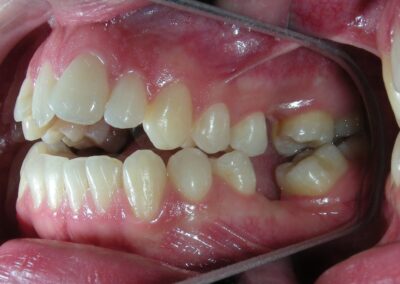

The patient presented with an anterior open bite, characterized by the absence of vertical overlap between the upper and lower incisors, and bilateral posterior crossbite. Extraoral examination revealed a vertically long facial pattern with an increased lower third of the face. The profile is convex with a retruded chin, indicating sagittal and vertical skeletal imbalances. We find also the inclined bipupillary line, which corresponds to facial asymmetries and altered occlusal plane.

Intraoral Examination:

Absent #16, #36 and #46 , No Angle molar relationship . Projection of canines axes in class II relationship . Anterior open bite: Over Bite – 8 mm). Bilateral posterior crossbite: Involvement of upper posterior sectors with inverted buccal-lingual relationship. Moderate Crowding at the level of the upper and lower incisors. Acceptable Oral Hygiene with no periodontal issues